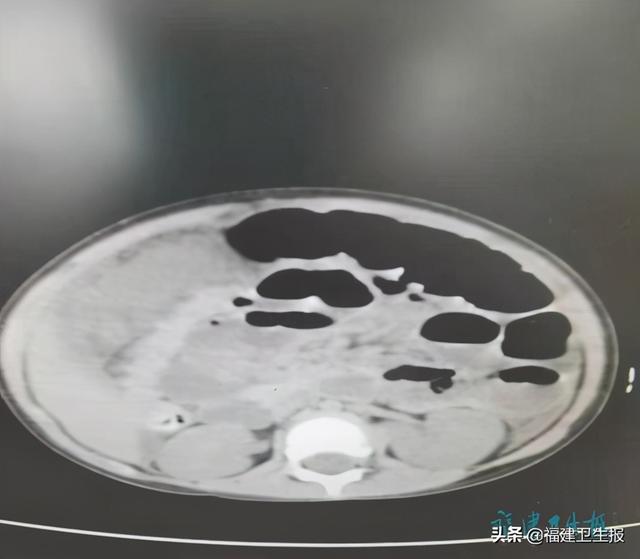

黄怃主任医师在接到请示后 , 为轩轩再次进行全面检查 。 凭多年经验 , 加之本月初他曾接诊过类似病症的患儿 , 立即告诉家属病情极其危重 , 患儿的病症应是腹腔肠梗阻或肠套引起的感染性休克 。 于是 , 对轩轩急查腹部CT , 结果显示 , 轩轩右中腹部小肠明显扩张、积液 。 为小肠梗阻征象 。

文章插图